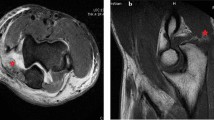

Axial, sagittal, and coronal images of 2.5-mm slice thickness and a 0.5-mm section spacing were acquired using T1-weighted and T2-weighted and proton density (PD) sequences, with and without fat suppression [18]. The protocol and parameters used in the MRI sequences are described in Table 2. The collateral ligaments of the elbow were visualized in a 20° posterior oblique coronal plane in relation to the humeral diaphysis with the elbow extended and a coronal plane aligned with the humeral diaphysis with the elbow flexed 20 to 30° (Fig. 1a–b).

UCL and LUCL alterations in signal and morphology on T1-weighted and T2-weighted imaging were suspected of ligament tear [19] (Figs. 2 and 3a–b). The UCL’s anterior bundle was evaluated in a coronal view, while the posterior bundle was well recognized and evaluated in axial view. The annular ligament of lateral collateral ligament (LCL) complexes was evaluated in axial and sagittal views; coronal and sagittal views were used for evaluation of the RCL and LUCL [20]. Protocol and parameters used in the MRI sequences of the elbow are reported in Table 2. Images were processed and elaborated using OsiriX DICOM Viewer 11.0 (Bernex, Switzerland).

a T2-weighted coronal and b sagittal PDW-SPAIR MRI showing a complete avulsion of LUCL from the humeral side (white asterisk). c, d Intraoperative view of LUCL avulsed from the humeral insertion (white asterisk). PDW, proton density weighted; SPAIR, spectral attenuated inversion recovery; MRI, magnetic resonance imaging; LUCL, lateral ulnar collateral ligament

a Coronal and b sagittal PDW-SPAIR MRI showing a partial tear of UCL (white asterisk) and complete tear of LUCL (white circle). c, d Intra-operative view showing partial tear of UCL (black asterisk), complete tear of LUCL (white circle), and integrity of RCL. PDW, proton density weighted; SPAIR, spectral attenuated inversion recovery; MRI, magnetic resonance imaging; UCL, ulnar collateral ligament; LUCL, lateral ulnar collateral ligament; RCL, radial collateral ligament

a, b Coronal T2-weighted and sagittal T2-weighted SPIR MRI view, showing a complete avulsion of flexor-pronator muscle (white asterisk) and LUCL (white circle) from the humeral origin, with posterior dislocation of the radial head. c Intra-operative view showing complete avulsion of flexor-pronator muscle from the medial epicondyle. d, e Coronoid fracture fixation with plate (white apex) and site of insertion of UCL on the medial facet of the humerus (white hashtag). f Complete avulsion of LUCL from the humerus (black circle). SPIR, spectral presaturation with inversion recovery; MRI, magnetic resonance imaging; LUCL, lateral ulnar collateral ligament; UCL, ulnar collateral ligament